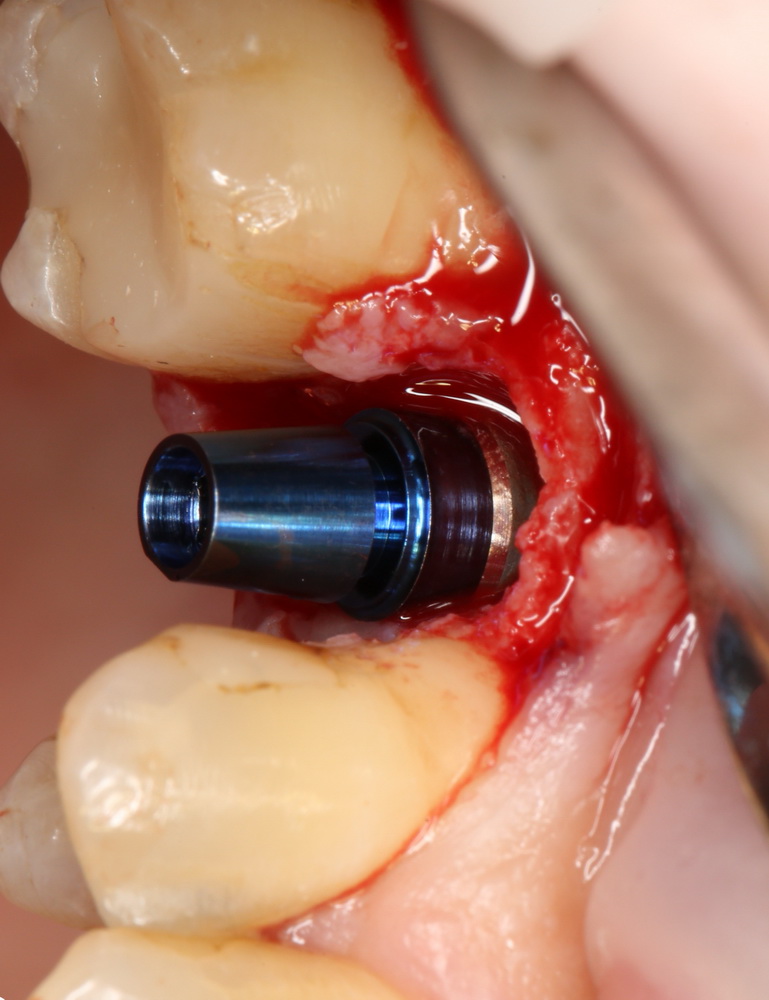

Затем лунка зуба адаптируется, в нее устанавливается имплантат, в данном случае Friadent XiVE диаметром 4.5 и длиной 13 мм:

Если не предполагается немедленная нагрузка (изготовление коронки на имплантат), первичная стабильность не является обязательной. Тем более, нельзя пытаться ее достичь, меняя положение и, особенно, погружение импланта. Если есть опасения, можно закрыть имплантат заглушкой, а саму лунку герметично ушить, используя свободный слизистотканный аутотрансплантат или (что разумнее) коллагеновую матрицу Mucograft Seal. Про последнюю обязательно расскажу вам, как только наберу достаточное количество клинических примеров.

Но в данном случае стабильность хорошая, на имплантат фиксируем формирователь десны, накладываем швы: